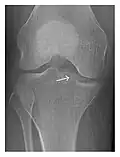

High-energy trauma fractures

Occult osseous injuries may result from a direct blow to the bone by compressive forces of adjacent bones against one another or by traction forces during an avulsion injury. Lesions in the tibial plateau, hip, ankle, and wrist are often missed. In a tibial plateau fracture, any disruption of the posterior and anterior cortical rims of the plateau should be sought. Impaction of subchondral bone will appear as an increased sclerosis of the subchondral bone (Figure 1). In the hip, posterior acetabular fractures also present subtle radiographic findings. The acetabular lines should then be carefully examined keeping in mind that the posterior rim, which is harder to see on X-rays, is more frequently fractured than the anterior rim (Figure 2). In the wrist, detection of carpal bone fractures is often challenging, with up to 18% of scaphoid fractures radiographically occult. Carpal fractures, especially the scaphoid, are associated with the risk of avascular necrosis. In apparently normal wrist radiographs from symptomatic patients, if there is history of a fall on an outstretched hand with pain in the anatomic snuffbox, suggesting scaphoid injury, the initial examination with posteroanterior, lateral, and pronation oblique views must be complemented by other specific views such as supination oblique and the "scaphoid" view A careful examination of cortices for evidence of discontinuity or offset and cancellous bone for lucency is necessary (Figure 3).[1]

Figure 1: A 56-year-old woman presenting with left knee pain after a fall. (a) Initial anteroposterior radiograph was considered normal, however, subtle cortical disruption of the anterior rim of the medial tibial plateau, medial to the tibial spine, is noted (arrow). (b) Coronal T1-weighted MRI confirms the cortical disruption (arrow) and shows extensive fracture through the proximal tibia. (c) Coronal proton density-weighted image with fat saturation shows extensive edema in the subchondral bone. Note also hypersignal adjacent to the medial collateral ligament corresponding to a grade I sprain (arrowheads).[1]